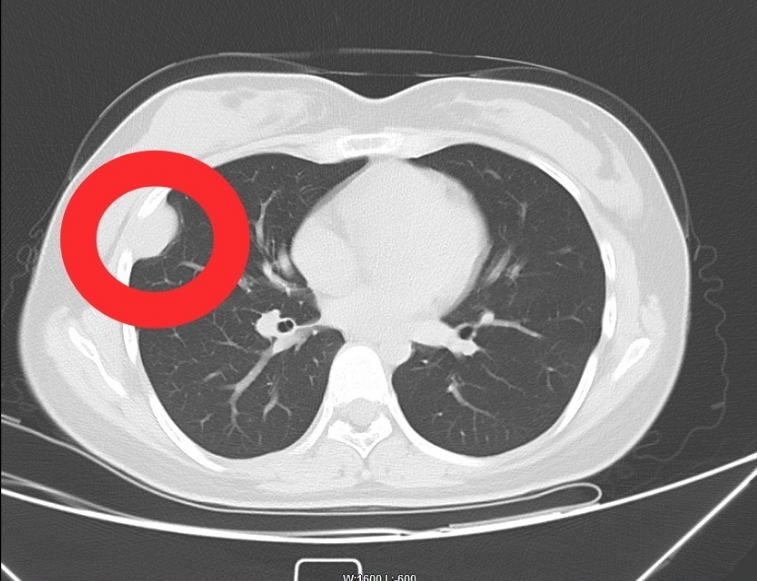

21岁的小高在过去一年中反复出现右侧胸部刺痛,辗转多家医院后通过CT及磁共振检查发现:胸壁处潜伏着一枚直径约4cm的神经鞘瘤。经多方打听,患者慕名来到常德市第四人民医院心胸乳甲血管外科就诊。

由于肿瘤位置特殊,与周围重要血管和神经关系密切,常德市第四人民医院胸外科团队经过周密术前讨论,为患者制定了详细的手术方案。在完善术前准备后,团队为患者施行了“胸腔镜下胸壁肿瘤切除术”。

术中可见肿瘤基底位于胸壁,与肋间神经关系密切。医生们精细操作,完整切除肿瘤,同时最大限度保护了周围正常组织。手术过程顺利,出血少。术中快速冰冻切片及术后病理检查证实为神经鞘瘤,性质为良性。患者恢复迅速,术后第一天即可下床活动,4天后康复出院。